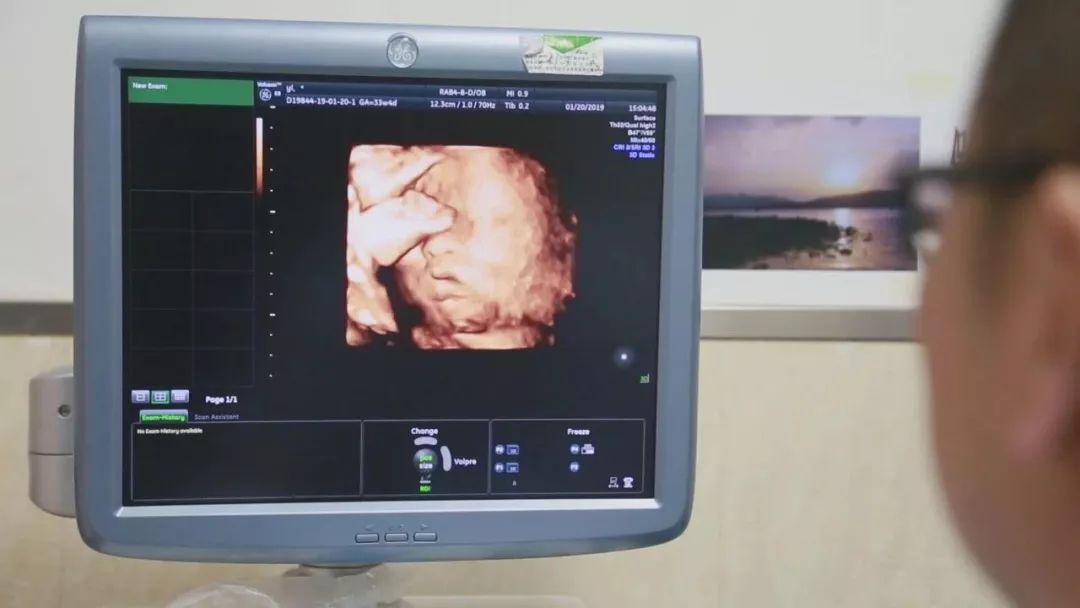

在对移植子宫连续监测后,为提高胚胎移植成功率,专家团队采取中西医结合的方法,改善杨华子宫内膜情况,为胚胎着床做好准备。2018年6月13日,妇产科王西林教授实时监测超声,在超声“慧眼”精确指引下,妇产科黄艳红教授谨慎翼翼地将冷冻胚胎植入移植的子宫内。14天后,复苏胚胎着床,杨华成功妊娠,这已是第五次尝试。妊娠早期,杨华出现妊娠剧吐、先兆流产的症状,妊娠中晚期出现胎儿生长受限,先后4次住院进行保胎等治疗。

整个孕期,为避免出现并发症、确保母婴健康,妇产科、泌尿外科专家团队结合杨华身体情况,制定了个体化免疫抗排斥用药等方案,并定期进行超声、血药浓度、激素水平等监测。根据监测结果,实时调整用药,保证胎儿羊水、体重、胎心等生长发育指标处于正常范围。